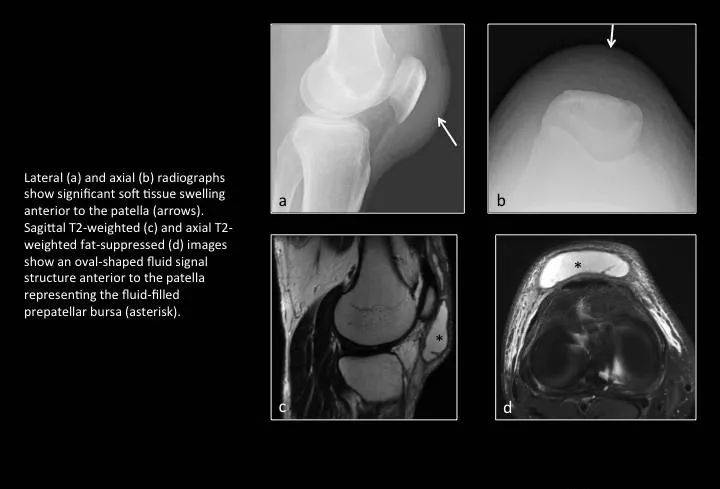

Fig. 22: Prepatellar bursitis

图22:髌前滑囊炎